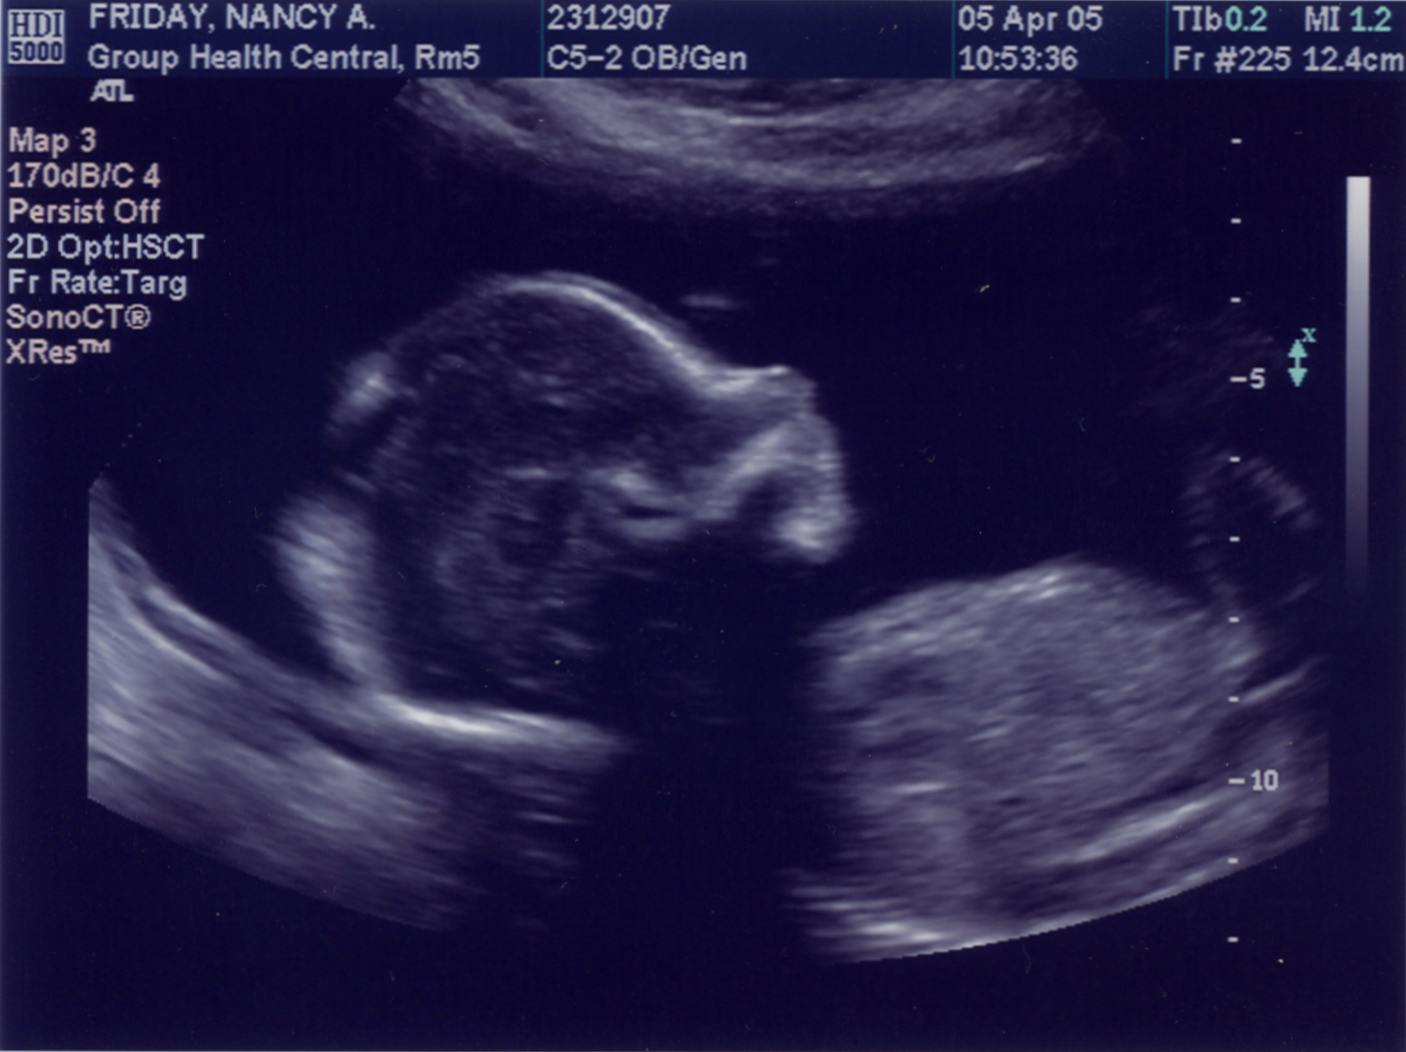

April 5, 2005 - 20.5 weeks (18.5 weeks from conception)  |